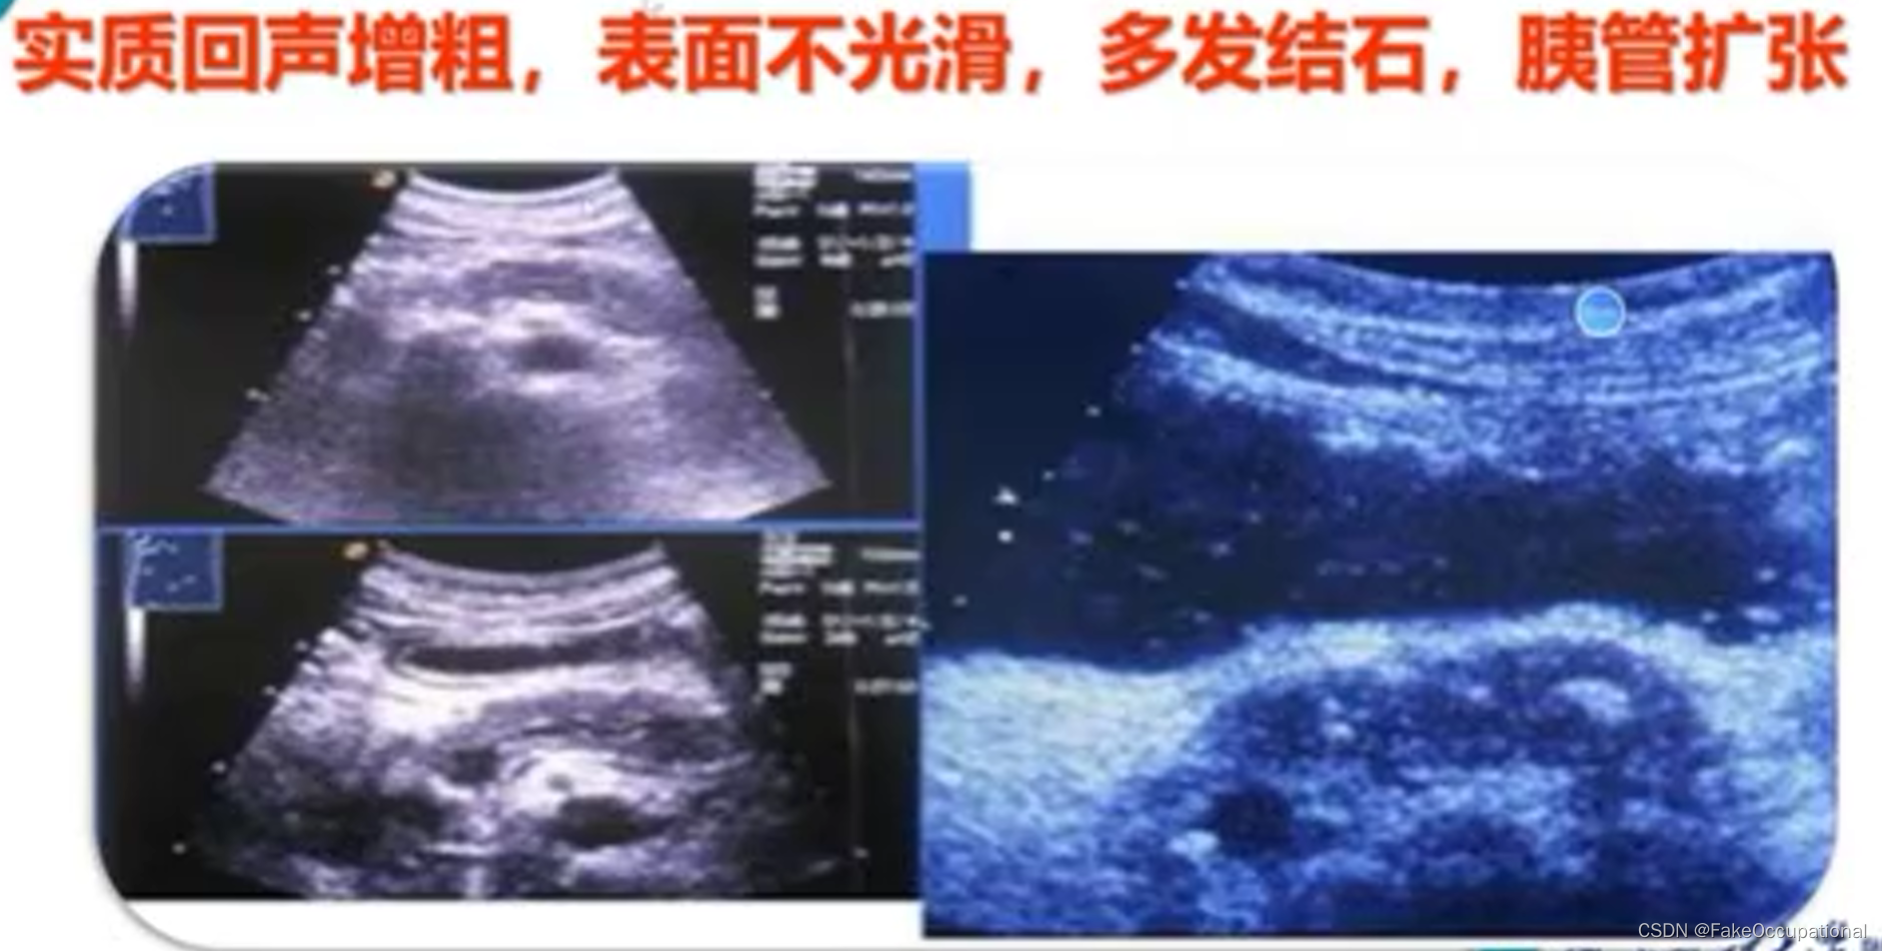

胰腺炎 — 急性胰腺炎、慢性胰腺炎

胰腺囊肿—假性囊肿、真性囊肿